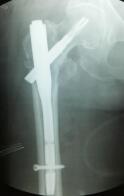

照片顯示骨折位置 運用內固定手術后

微創(chuàng)切口+“半瓶墨水”出血量,手術臺上,患者為醫(yī)生“點贊” 當天下午,在醫(yī)院麻醉科等科室的高效配合下,由吳東海主刀,為老人實施微創(chuàng)下的右股骨粗隆間骨折閉合復位PFNA(股骨髓內釘)內固定術。

術中,在X線機透視下,手法準確復位——切開幾個小口植入PFNA——將骨折固定穩(wěn)定——縫合切口。這一系列動作一氣呵成,手術僅用時20分鐘,手術切口總共5針,出血量很少,僅有差不多半瓶墨水的出血量,全過程只有輕微注射穿刺的疼痛。醫(yī)生高效、精準的手法,贏得了患者的稱贊。在手術結束時,薛大爺豎起雙手大拇指為醫(yī)生的精湛技藝比贊,醫(yī)生也為樂觀、勇敢的薛大爺比贊。這一幕溫情默默地流淌在手術間,讓原本讓人覺得冰冷的手術間不再冰冷。